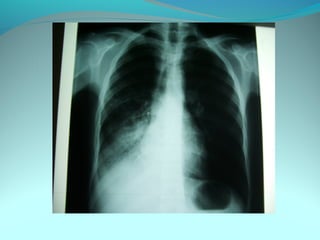

Opacité occupant la partie externe du 1/3 infer du poumon droit

dense et homogene ovalaire de 8cm de grand axe vertical

La limite externe se confend avec une opacité d’environ 1cm comble

les coupole costodiaphragmatique droit

Limitée a sa partie sup par la petit sessure qui est epaisse et pas de

lyse costale

 DIAGNOSTIC :DIAGNOSTIC :

 1_1_cancer bronchique droit( d epaississement)

 2_2_ kyste hydatique au stade sain